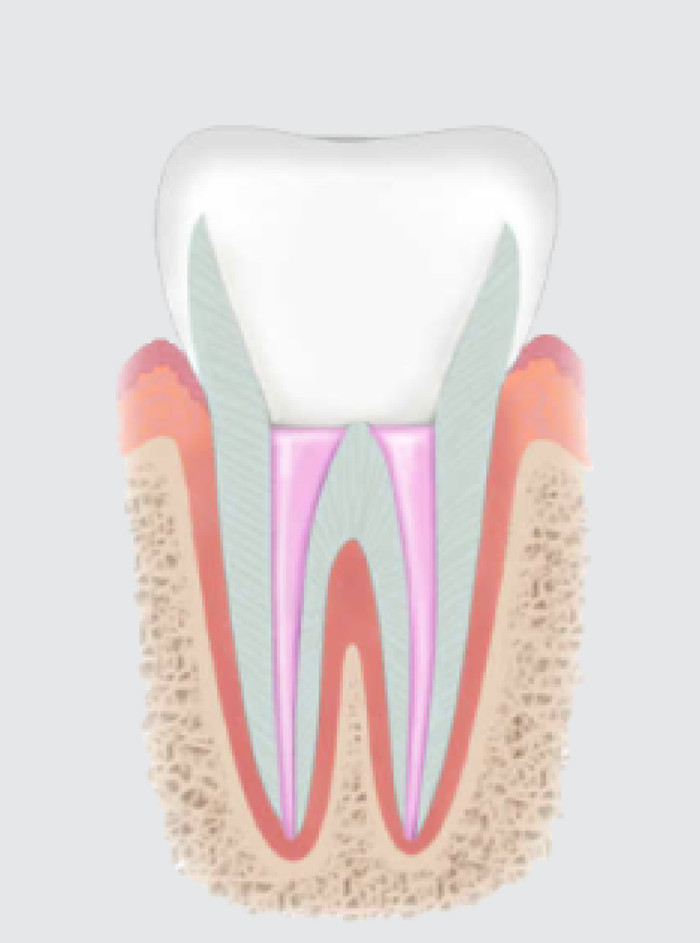

신경치료 과정

충치가 심해서 신경치료를 하게 되는 경우 먼저 치아의 충치를 모두 제거하고 치수까지 구멍을 뚫습니다. 이 공간을 통해서 치아의 뿌리 부위까지 안 쪽에 있는 치수(신경 조직)을 모두 제거하고 일정한 크기로 확대시킨 후 치과용 생체 적합 재료로 채워 넣습니다. 신경치료를 마친 치아는 약해져서 부러지기 쉽기 때문에 크라운 치료를 해줘야 합니다.

• STEP 01

심한 충치로 인해 신경조직이 감염되어 신경치료가 필요한 상태입니다.

• STEP 02

치아 겉면의 충치와 염증이 생긴 내부의 신경조직을 제거합니다.

• STEP 03

깨끗이 제거된 내부의 신경관을 소독한 후 충전 재료로 채웁니다.

• STEP 04

신경치료 후 손상되기 쉬운 치아를 보호하기 위해 크라운을 씌웁니다.